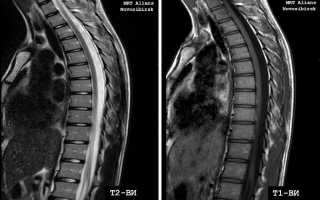

Магнитно-резонансная томография (МРТ) грудного отдела позвоночника — это информативный метод диагностики, позволяющий получить детализированные изображения позвоночника и окружающих тканей. В статье рассмотрим показания к МРТ, преимущества метода и возможные патологии, которые можно выявить. Понимание особенностей МРТ грудного отдела позвоночника поможет читателям ориентироваться в диагностике и лечении заболеваний этой важной части опорно-двигательного аппарата.

МРТ грудного отдела позвоночника является важным инструментом в диагностике различных заболеваний и травм. Эксперты отмечают, что этот метод позволяет получить высококачественные изображения мягких тканей, межпозвоночных дисков и нервных корешков, что особенно полезно при подозрении на грыжи, остеохондроз или опухоли. По мнению специалистов, МРТ помогает не только в выявлении патологии, но и в оценке степени её тяжести, что способствует более точному выбору методов лечения. Кроме того, отсутствие ионизирующего излучения делает МРТ безопасным для пациентов, что особенно важно при необходимости многократных исследований. В целом, эксперты подчеркивают, что МРТ грудного отдела позвоночника является незаменимым методом в современной медицинской практике.